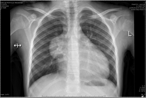

Anterior mediastinal teratoma with pericardial effusion. Rare presentation

Moaath Al Smady and others

Journal of Surgical Case Reports, Volume 2019, Issue 5, May 2019, rjz136, https://doi.org/10.1093/jscr/rjz136